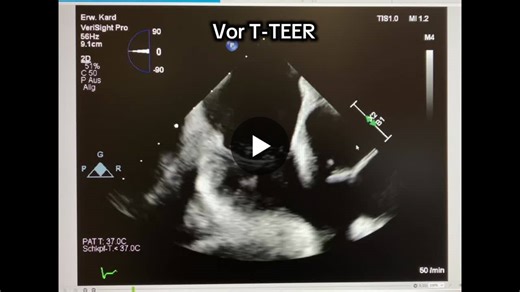

#structuralheart #tteer #tricuspid #pascal #ice #3dice #verisightpro